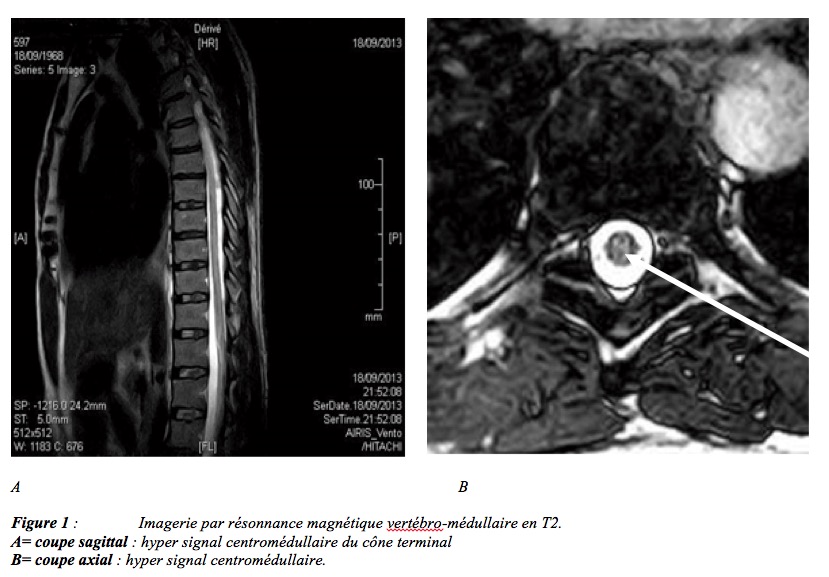

A son admission, il était conscient, coopérant, apyrétique avec un état hémodynamique normal et stable. Nous avons observé une paraparésie avec une force motrice estimée à 3/5, une abolition des réflexes rotuliens et les réflexes cutanéo-plantaires étaient indifférents des deux côtés. Il n’y avait pas de trouble sensitif objectif ni de signe d’irritation méningée. Son bilan biologique a révélé une discrète hyperleucocytose (11000/mm3) à prédominance neutrophile (8,5/mm3) et une CRP négative. Il a bénéficié d’une oxygénothérapie à 12 l/mn, une hyperhydratation à 3 l/24 heures pendant 72 heures. L’évolution à 72 heures, a été marquée par l’aggravation des signes avec une paraplégie, une hypoesthésie à tous les modes avec un niveau sensitif T10, une incontinence anale et une impuissance. L’imagerie par résonnance magnétique nucléaire réalisé à J4 a permis de mettre en évidence un hyper signal en T2 au niveau du cône terminal de la moelle épinière (figure 1, 2).

Les ADD sont très rares. En France leur incidence est estimée à 1 accident pour 15000 plongées [2]. En Afrique, Landsberg a rapporté 59 cas entre 1969 et 1977 en Afrique du sud [3] et Messelmani a dénombré 9 cas d’ADD médullaires en Tunisie, entre 2007 et 2012 [4]. Au Bénin, aucun cas n’a été rapporté. Sur le plan physiopathologique, en plongée, les gaz diluants présents dans l’air (principalement l’azote) se dissolvent dans le sang et les tissus en fonction de la pression hydrostatique et de la durée du séjour dans l’eau selon la loi énoncée par William Henry en 1803. Lors de la remontée, les gaz dissouts dans les tissus sont restitués au milieu sous forme de bulles. Lors de la désaturation du plongeur, l’élimination d’azote s’accompagne souvent de bulles circulantes dans le réseau veineux normalement éliminées par les poumons [5,6]. En cas d’accident de décompression, l’afflux des bulles est massif dépassant la capacité d’élimination du réseau capillaire pulmonaire entraînant leur stase dans la petite circulation. Il s’en suit une hypertension artérielle pulmonaire responsable d’une augmentation des pressions dans les cavités cardiaques droites. Celle-ci retentit particulièrement sur les plexus veineux épiduraux par la constitution d’un obstacle sur le drainage veineux de la moelle épinière [7,8,9]. Ainsi l’ischémie médullaire est le plus souvent d’origine veineuse. Lorsque la capacité du filtre pulmonaire est dépassée, on assiste à un passage de bulles dans la circulation systémique favorisée par la persistance d’un foramen ovale perméable [10]. Ces bulles sont responsables d’embolies gazeuses artérielles pouvant être à l’origine d’accidents ischémiques cérébraux, cochléo-vestibulaires mais également médullaires. Ceci explique l’origine artérielle possible de l’ischémie médullaire dans l’accident de décompression [11]. Les bulles provoquent des phénomènes d’occlusion micro-vasculaire et des lésions endothéliales avec activation de la coagulation et de l’inflammation. Ces phénomènes déclenchent une maladie qui évolue pour son propre compte c’est la maladie de décompression [12]. L’âge de notre patient supérieur à 42 ans et son manque d’entraiment font partie des facteurs favorisants la survenue des ADD [12]. Sur le plan clinique, on distingue 2 types d’ADD. Le type 1 regroupe les accidents cutanés et ostéo-myo-articulaires. Le type 2 regroupent les accidents neurologiques (médullaires, cochléo- vestibulaires, cérébraux), et plus rarement les accidents pulmonaires, les accidents cardiaques, et les manifestations générales. Les plus fréquents et les plus graves sont les accidents neurologiques (environ 89% des cas) [12]. Les ADD médullaires, comme celui qu’a présenté notre patient, représentent 66% des formes cliniques rapportées par Blatteau sur une série de 61 cas [12]. Notre patient a tous les éléments cliniques de gravité des ADD médullaires : l’âge supérieur à 42 ans, les douleurs vertébrales, l’aggravation progressive des signes, l’hypoesthésie, la paraplégie et l’atteinte du sphincter urinaire. La présence d’hyper-signal et T2 à l’IRM médullaire est un l’élément radiologique de mauvais pronostique [13]. Sur le plan thérapeutique, l’objectif essentiel du traitement d’un accident neurologique de décompression est de limiter l’ischémie tissulaire, en s’attaquant à la cause (les bulles) et aux conséquences (maladie de décompression). Il repose essentiellement sur l’oxygénothérapie hyperbare et la réhydratation.